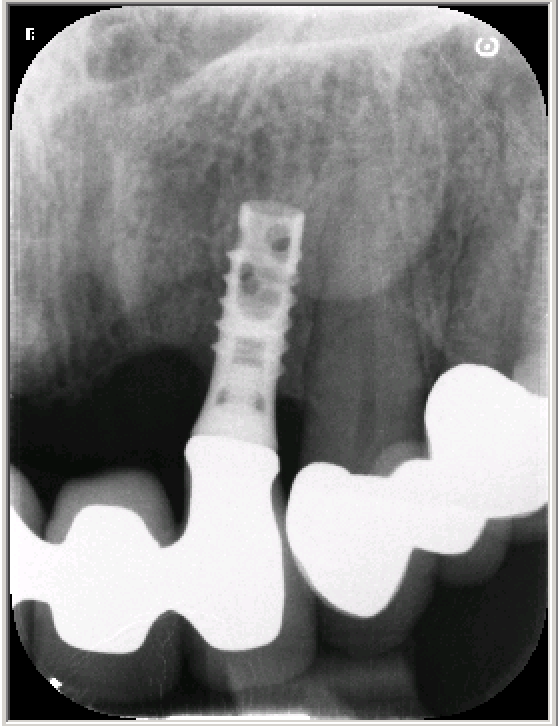

Información sobre el implante

Queridos compañeros, queremos saber que tipo de Implante, marca ,medida o cualquier otra información sobre este implante.Un saludo, gracias.